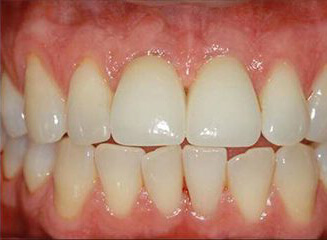

Probleem. Laiad hambavahed ja katkised hammaste servad.

Lahendus. 4 hamba esteetiline täitmine.